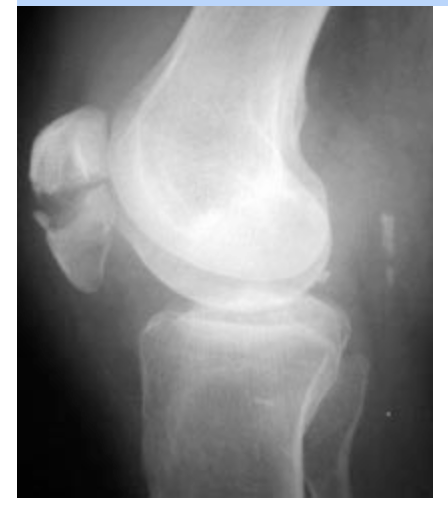

What bone is fractured in this patient? (Image attached)

Patella